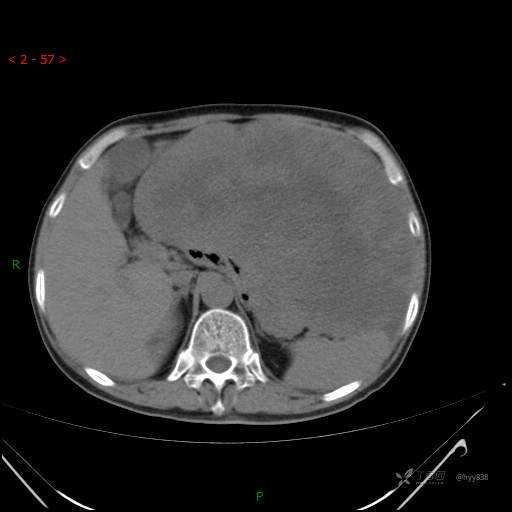

增强静脉期